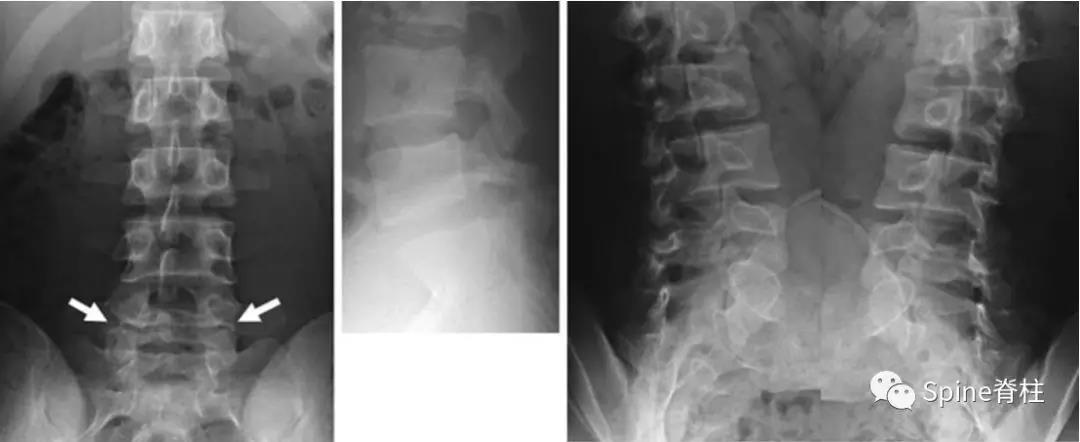

2003年发表在Am J Sports Med杂志(IF=6.20)上的病例报道,很好的阐述了峡部裂和椎弓根裂的变化。描述一个17岁的棒球运动员,运动后腰痛1月余,随访的辅助检查提示相同椎体水平出现的3个连续性应力性骨折:第一次为左侧峡部,第二次为右侧椎弓根,第三次为右侧峡部。

图:起始CT提示L5左侧峡部裂(双箭头),起始CT检查后2个月复查可见出现右侧椎弓根裂(单箭头),4个月复查可见椎弓根裂愈合(单箭头)